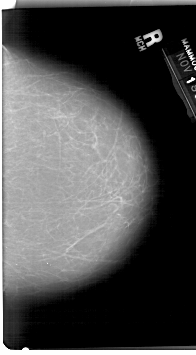

A_1413_1.LEFT_MLO

A_1413_1.RIGHT_MLO

A_1413_1.LEFT_CC

A_1413_1.RIGHT_CC

LEFT_CC LINES 5986 PIXELS_PER_LINE 3721 BITS_PER_PIXEL 12 RESOLUTION 43.5 OVERLAY

LEFT_MLO LINES 6511 PIXELS_PER_LINE 4066 BITS_PER_PIXEL 12 RESOLUTION 43.5 OVERLAY

RIGHT_CC LINES 6736 PIXELS_PER_LINE 3721 BITS_PER_PIXEL 12 RESOLUTION 43.5 NON_OVERLAY

RIGHT_MLO LINES 6646 PIXELS_PER_LINE 3331 BITS_PER_PIXEL 12 RESOLUTION 43.5 NON_OVERLAY

FILE: A_1413_1.LEFT_MLO.OVERLAY

TOTAL_ABNORMALITIES 1

ABNORMALITY 1

LESION_TYPE MASS SHAPE OVAL MARGINS ILL_DEFINED

ASSESSMENT 4

SUBTLETY 5

PATHOLOGY BENIGN

FILE: A_1413_1.LEFT_CC.OVERLAY